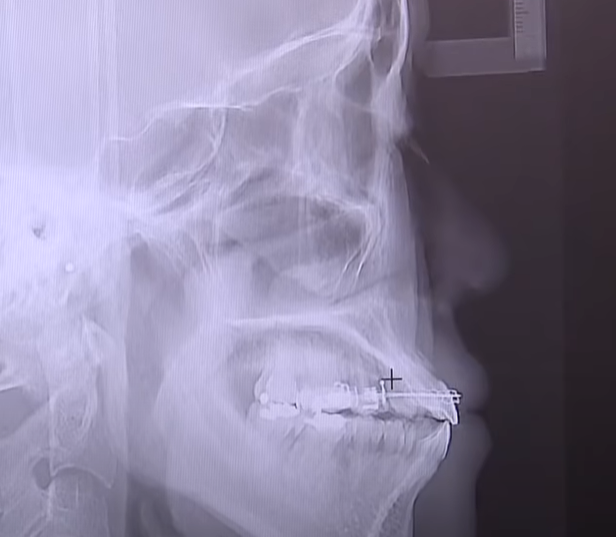

교정 치료 중 잇몸 퇴축 방지

교정 치료는 치아를 이동시키는 과정으로,

이 과정에서 과도한 압력이 잇몸에 가해질 경우 잇몸 퇴축을 유발할 수 있습니다.

교정 치료를 좀 더 천천히 진행하거나 잇몸 퇴축을 미리 예방하기 위한 조치를 취하는 것이 중요합니다.

특히, 잇몸이 얇은 사람들은 자극에 더 민감하므로 주의가 필요합니다.